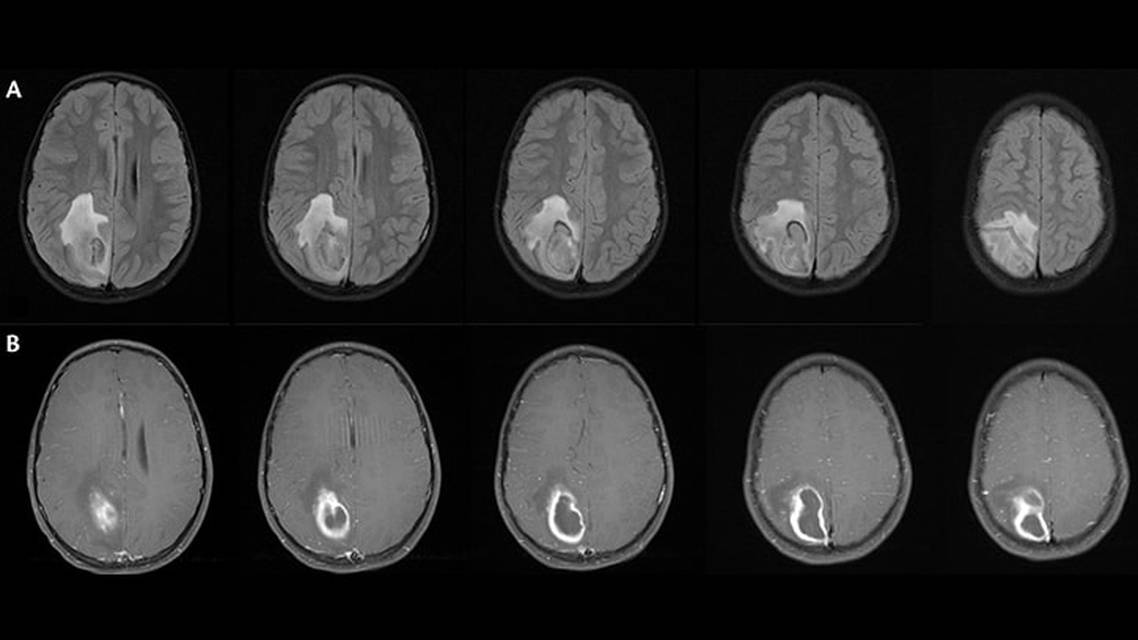

Focal Status Epilepticus 9 Years After Brain Abscess

In a retrospective study of 205 individuals followed after brain abscess for 22 years, 17% had acute symptomatic seizures, 6.4% had delayed seizures, and none developed seizure more than 3 years after bacterial brain abscess.2 The case presented here is atypical in that 9 years elapsed between brain abscess and the first seizure. Considering the prolonged time lapse, we hypothesized Mr B had an area of gliosis from his prior brain abscess that was somehow irritated after a fall. Alternatively, he may have had a first focal seizure with paresthesia causing the fall while skiing, and never suffered a head injury.

Seizures are a common sequela of brain abscess, and although most are acute and symptomatic, some progress to epilepsy. Typically, when epilepsy develops, it presents within the first 3 years after brain abscess. We present a unique case of late-onset, lesional epilepsy localizing to a prior brain abscess resection site. The seizures started in setting of a fall and were possibly triggered by inflammation secondary to mild head trauma. After no response to typical ASMs, seizure control was achieved with methylprednisolone and fosphenytoin.